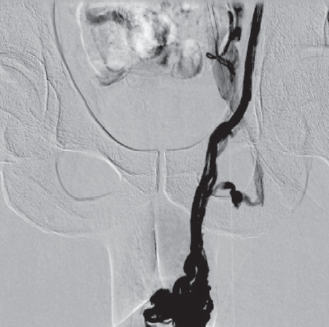

Гипертензия в бассейне левой общей подвздошной вены вследствие ее компрессии между правой общей подвздошной артерией и телом пятого поясничного позвонка (синдром Мея – Тюрнера) является причиной венозного полнокровия органов малого таза (рис. 4) и ретроградного кровотока по вене мышцы, поднимающей яичко в гроздевидное сплетение яичка и его придатка (илеосперматический тип варикоцеле) (рис. 5).

Рис. 4. Антеградная илеокаваграфия. Нетромботическая компрессия левой почечной вены. Коллатеральное кровообращение и выраженное венозное полнокровие органов малого таза

Fig. 4. Antegrade ileocavagraphy. Non-thrombotic compression of the left renal vein. Collateral circulation and pronounced venous congestion of the pelvic organs